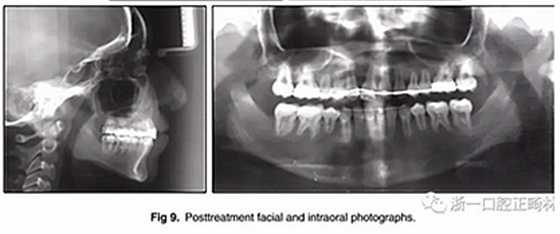

兩年半后,在上下牙弓上均實現(xiàn)了間隙關(guān)閉,并且使用0.017×0.025英寸的不銹鋼弓絲進(jìn)行咬合精細(xì)調(diào)整(圖8)。去除托槽后,上下頜采用舌側(cè)弓進(jìn)行保持(圖9)。

總體治療目標(biāo)已經(jīng)實現(xiàn)。病人的笑容和輪廓有所改善。咬合關(guān)系為I類磨牙關(guān)系,牙列整齊,牙尖交錯關(guān)系良好。反合和中線偏移得以矯正,并實現(xiàn)了正常的覆蓋和覆合。上下牙弓的擁擠問題完全解決,并且完成后全景片顯示良好的牙根傾斜度。疊加顯示良好的縱向和垂直控制(ANB,3.5°; SN / GoMe,42.5°)和矯正上下頜前牙傾斜度(1 / SN,96°; IMPA,87°)(圖10 ; 表)。

在治療結(jié)束時沒有觀察到顳下頜關(guān)節(jié)紊亂的體征或癥狀,但發(fā)現(xiàn)了輕微的牙根吸收以及裂隙區(qū)域的骨頭輕度丟失。

治療持續(xù)3年,患者始終保持積極和合作。口腔衛(wèi)生很好?;颊吆退母改付紝Y(jié)果感到滿意。